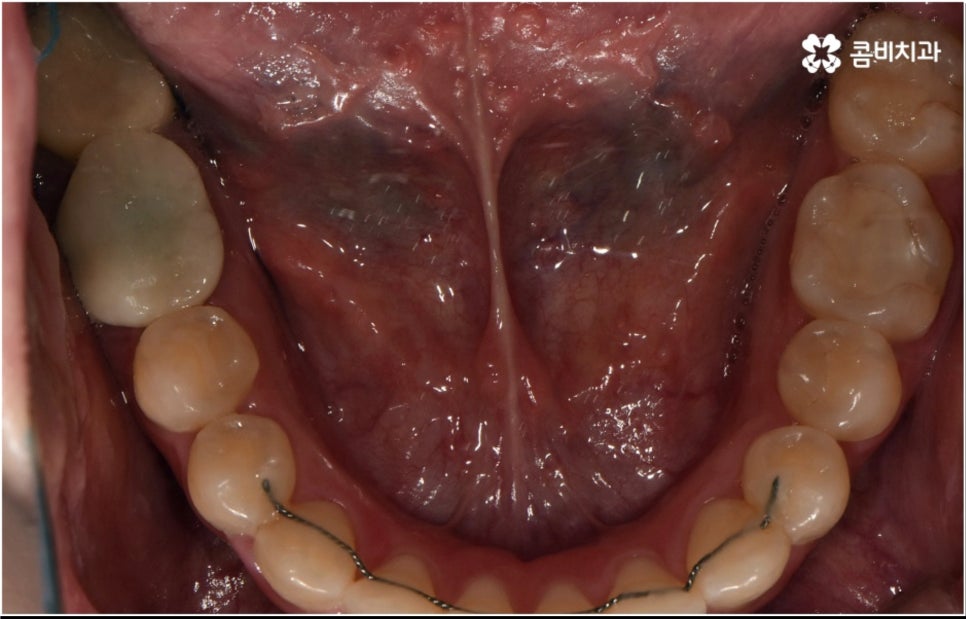

3D CT 등 정밀 검진 기계를 통해 꼼꼼하게 검진을 한 후 환자분들의 부정교합의 종류 및 정도 등에 따라 각자에게 맞는 교정 치료 계획을 수립하게 되는데, 내부 공간이 얼마나 있는지에 따라 발치가 필요한지 아닌지 여부도 달라지고 또 같은 부정교합이라고 해도 사람마다 잇몸 건강이나 치근 상태 등에 따라 잇몸뼈가 벌어지면서 치아가 이동하는 속도, 치아가 자리잡는 양상 등도 모두 달라지기 때문에 성인 치아교정 기간 총 소요 시간은 모두 달라질 수 밖에 없을 거예요.

물론 일반적으로 성장기보다는 잇몸뼈가 굳어진 이후 성인 치아교정 기간 이 길어질 수 밖에 없으나 이 역시 케이스별로 달라질 수 있어요. 예를 들어 만약 임플란트를 심으려고 할 때 공간이 없거나 주변 치열이 삐뚤어져서 어려움이 있기 때문에 하는 교정이거나 앞니 일부가 조금 벌어지고 살짝 각도가 앞으로 나와 있는 등 별다른 골격적 문제 없이 기능성 및 심미성을 보다 개선해 주기 위해서 하는 교정의 경우는 부분 교정으로 진행하기 때문에 보통 발치 과정도 포함되지 않고 성인 치아교정 기간 도 6~8개월 정도로 보다 빠르게 끝날 수 있습니다.

하지만 부정교합의 정도가 심하거나 골격적 문제를 바로잡아 주어야 하는 경우는 전체 교정을 진행해야 하기 때문에 (환자분들마다 다르지만) 평균적으로 18~36개월 정도의 성인 치아교정 기간 이 소요되며, 중장년 성인분들 중에 잇몸 질환 등으로 구강 건강이 약해져 있는 분들의 경우에는 더욱 환자분들의 상황에 맞게 필요한 치료를 병행하면서 무리하지 않은 진행을 해야 하기 때문에 전체 기간이 좀 더 늘어날 수 있어요.

성인 치아교정 기간 이 길어지면 생활상 또는 업무상 활발한 대인 관계를 맺고 있으신 분들의 경우 교정 장치가 눈에 띄는 문제 때문에 불편함을 느끼실 수 있어요. 하지만 최근 관련 기술의 발달로 장치들 역시 심미성이 뛰어난 것들이 많이 개발되었으며 선택의 폭이 넓어졌기 때문에 치료 과정 중에도 이러한 부담감을 줄이고 보다 만족도를 높일 수 있습니다.

치아 색상의 세라믹 브라켓을 이용하는 장치들은 예전 메탈 장치 보다 심미성이 훨씬 보완되었으며, 치아 뒤쪽에 장치를 부착하여 아예 눈에 띄지 않는 설측교정장치나 언뜻 보면 티가 잘 나지 않는 얇고 투명한 특수 강화 플라스틱을 이용하는 투명교정장치를 이용하면 교정을 하고 있다고 본인이 말을 하지 않으면 잘 모를 정도로 심미성이 뛰어나기 때문에 각 장치들의 소재와 특성, 장단점에 대해서 잘 알아보고 신중한 선택을 하는 것이 중요하다고 할 수 있어요.